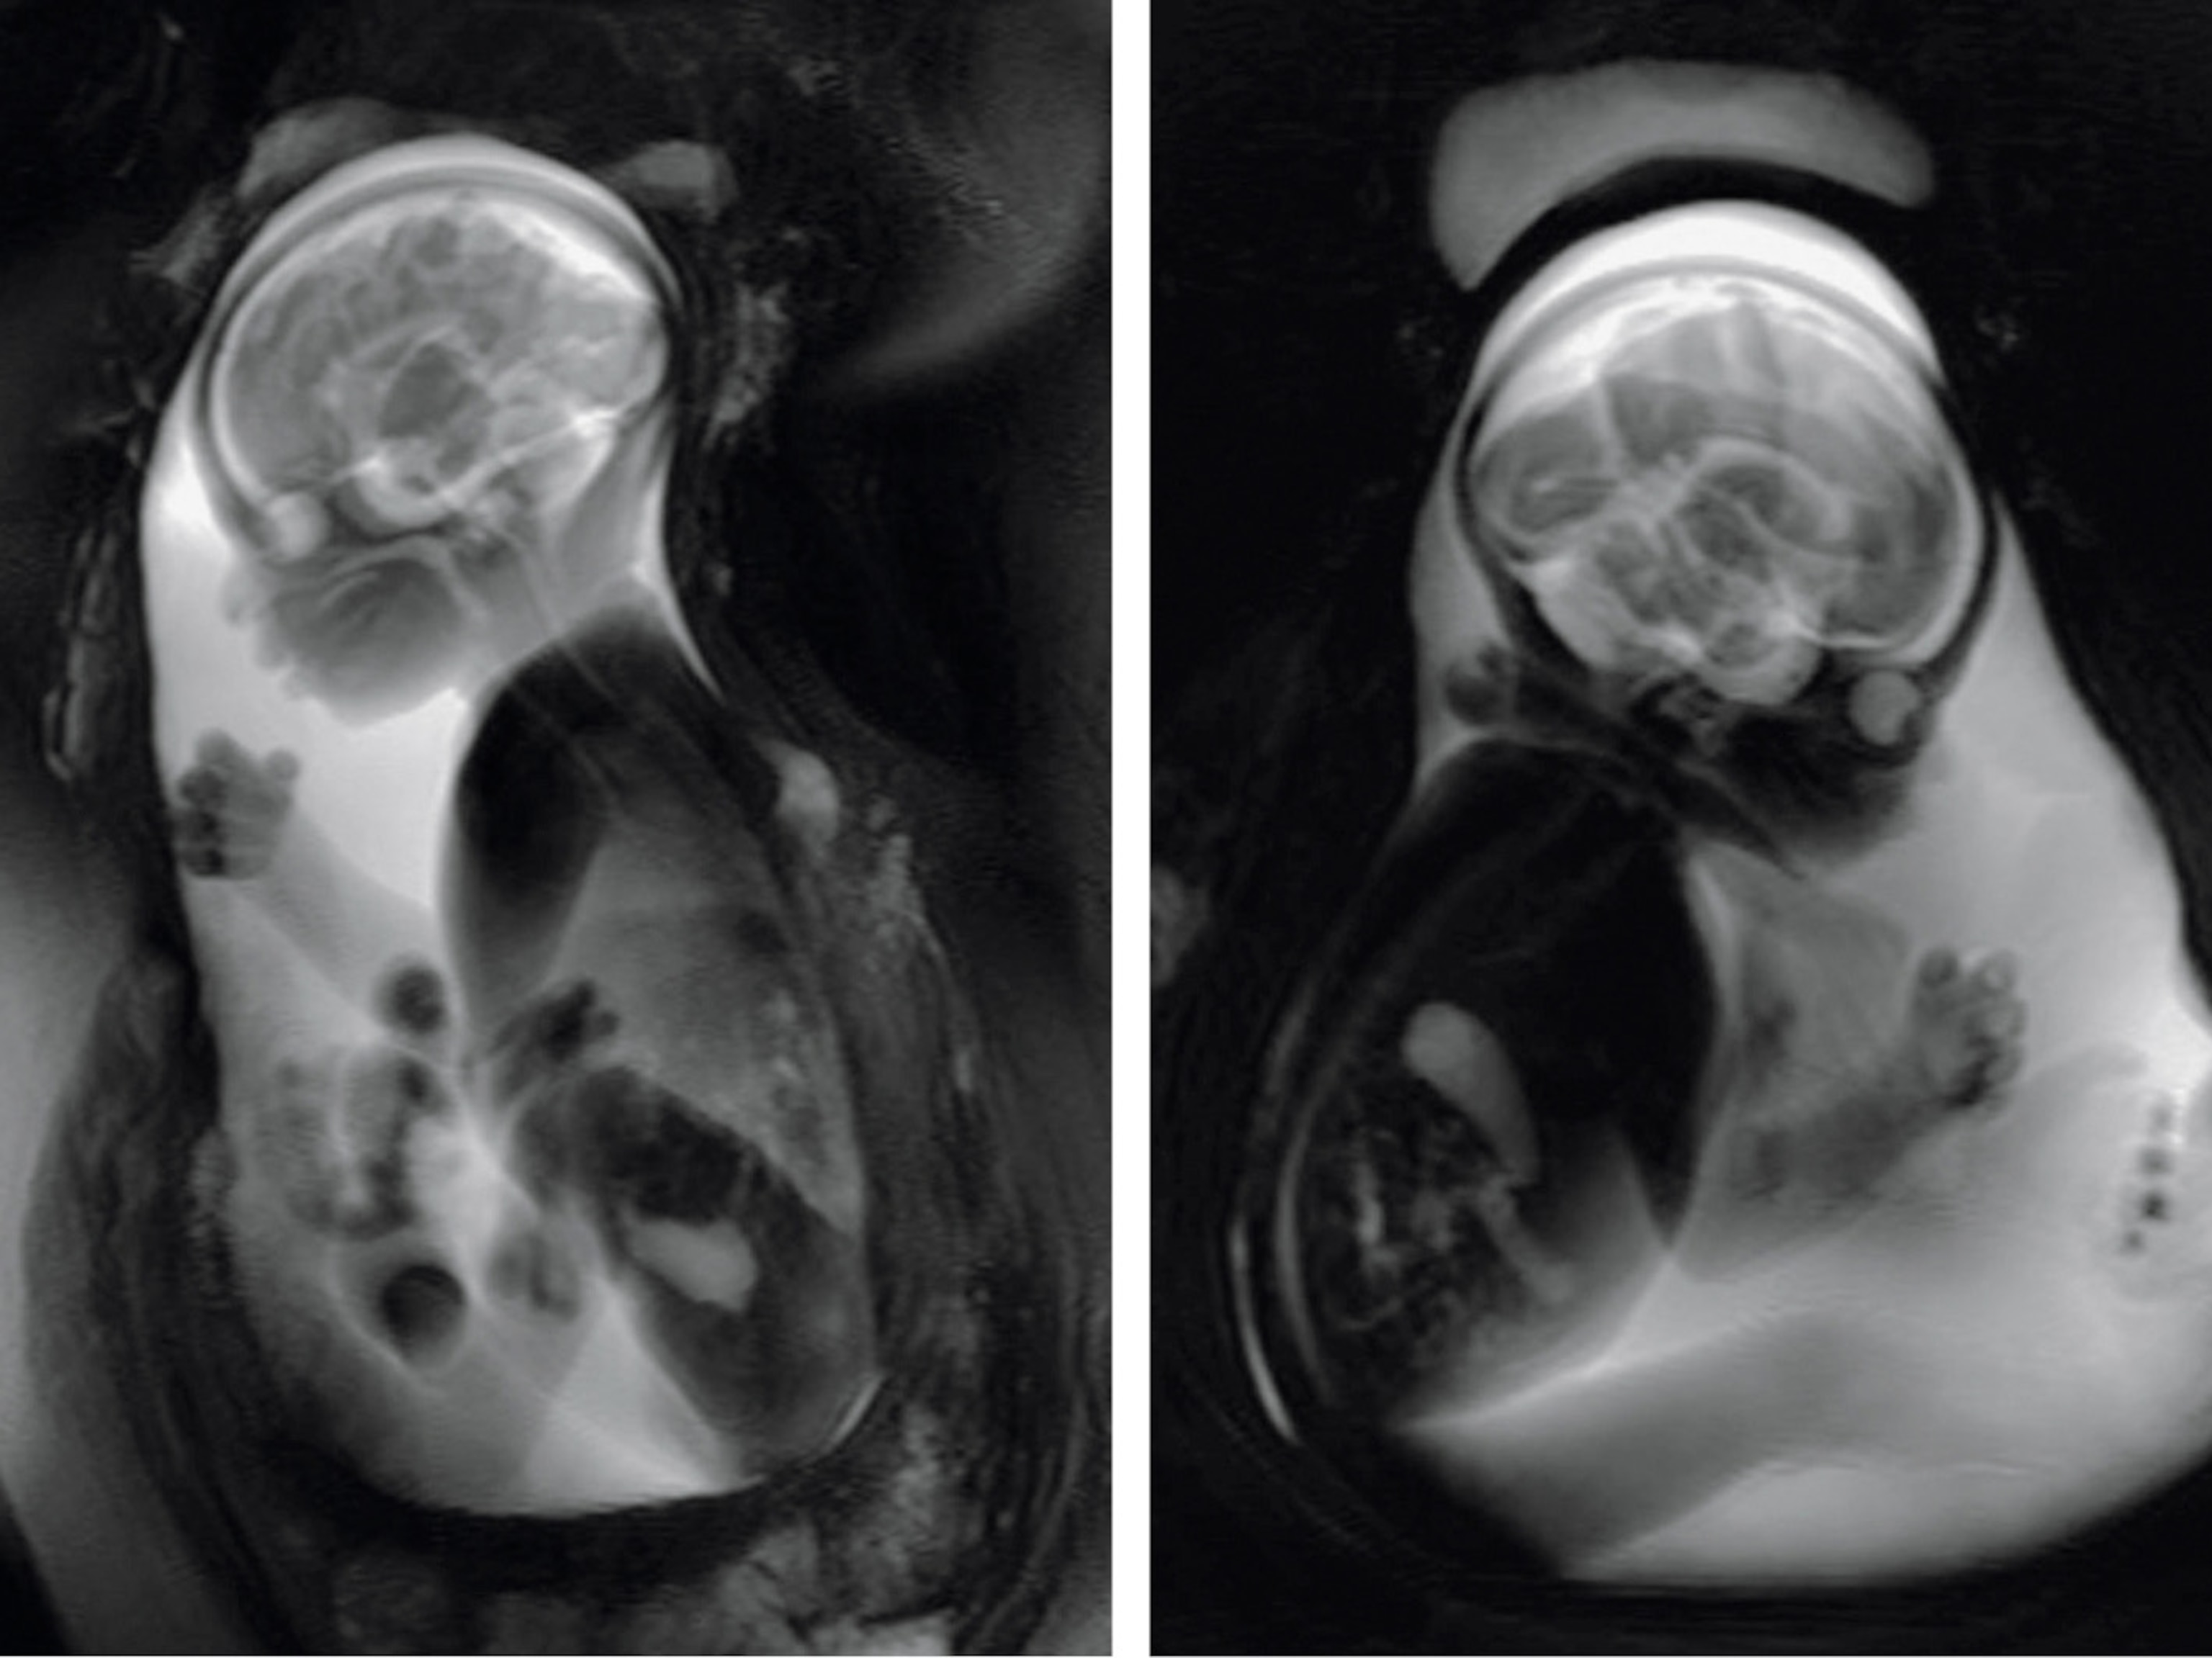

For 13-year-old Jahi McMath of Oakland, California, brain death was declared in the wake of complications from surgery. Her parents have fought to keep her on life support, contending that the functioning of her heart and lungs indicates she is still alive. In Texas, Marlise Munoz, a 33-year-old pregnant woman, collapsed at home and was subsequently termed brain dead at the hospital, according to her family. She remains on life support despite family wishes to turn off the ventilator; the hospital says it is following a state statute that prohibits removing life support from a pregnant patient so as to maintain the viability of the fetus.